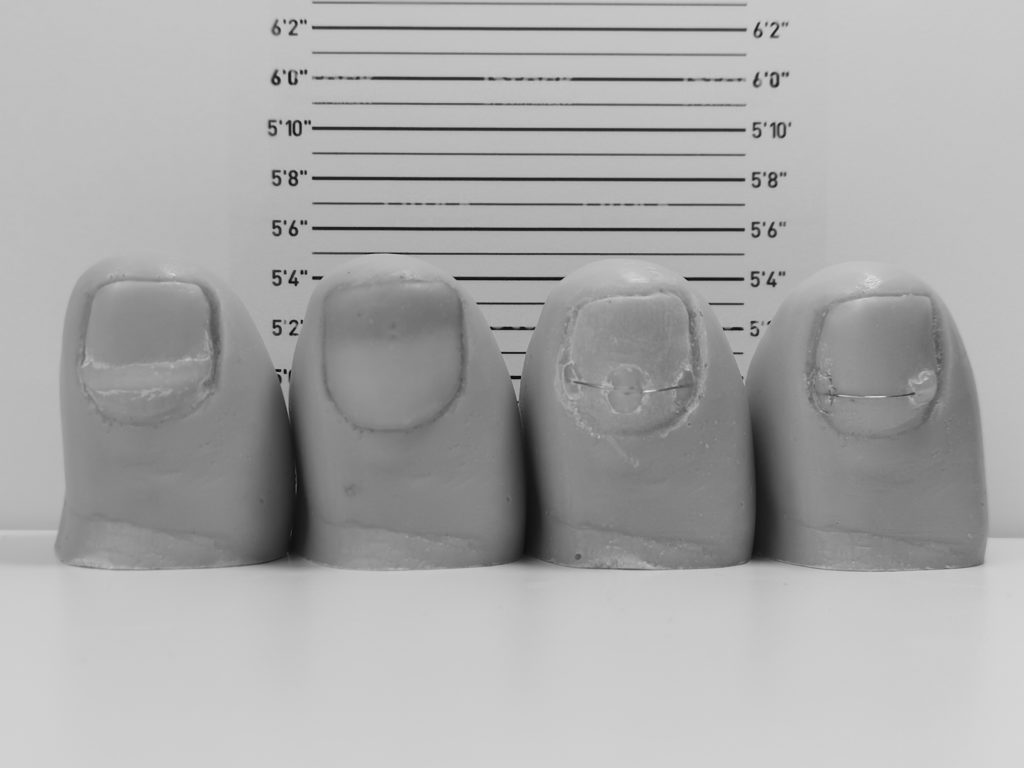

L’orthonyxie est un appareillage inspiré de l’orthondontie. Il est constitué d’encrages en résine photopolymérisable et d’un fil à mémoire

de forme. En effet, l’orthonyxie consiste à fixer sur l’ongle un fil titane positionné entre deux ou trois plots lui permettant de créer une

tension constante et contraire à la déformation de l’ongle. L’ongle s’aplanit alors au fur et à mesure de la repousse.

En fonction de la qualité et de l’importance de la déformation de l’ongle, plusieurs techniques sont envisageables : contention passive (languette de décompression) ou contention active (fil titane à traction unilatérale ou bilatérale).